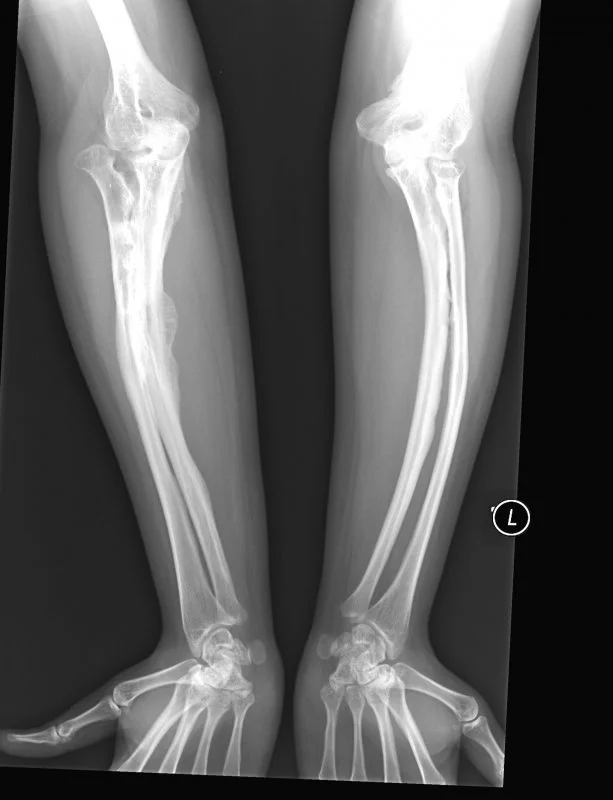

La osteogénesis imperfecta (OI) es un trastorno genético del tejido conectivo que afecta principalmente los huesos, causando fragilidad y susceptibilidad a fracturas. También se conoce comúnmente como «huesos de cristal». Esta enfermedad es causada por mutaciones genéticas que afectan la producción de colágeno, una proteína esencial para la fortaleza y elasticidad de los huesos.

Existen varios tipos de osteogénesis imperfecta, que varían en gravedad. Los síntomas comunes incluyen huesos frágiles y propensos a fracturas, deformidades óseas, dificultades en la movilidad, problemas de audición y otros problemas de tejidos conectivos como laxitud ligamentosa. La gravedad de la condición puede variar significativamente, incluso entre individuos afectados por la misma mutación.